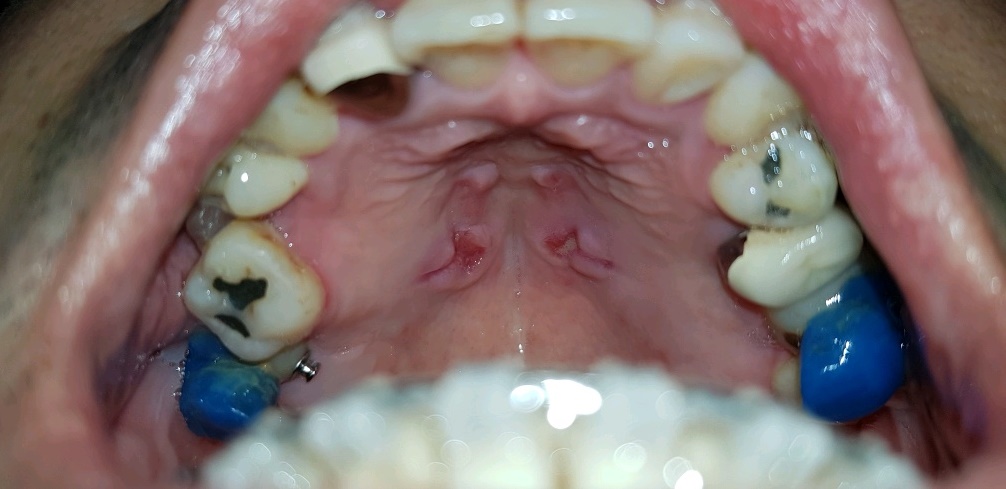

위 사진이 입천장에 작은 나사 4개를 박아서 입천장에 단단히 고정된 상태로 중앙에 나사 돌리는 곳이 있는데 쇠붙이같은걸 끼워서 양쪽 어금니 포함 4개를 쇠의 힘으로 조금씩 벌어지게 해서 치아들의 자리를 잡는 과정.

이걸 박고나서 일주일정도 고통이 지속됬던 것 같다.

(처음 몇일은 잠을 못잘 정도로 드럽게 아팠다;;)

입천장과, 쇠철판? 부분을 살짝 띄워놔서 공간이 있는데 양치하거나, 가레침이 들끓을 때 가레도 잘 못뱉고, 밥먹을 때도 온갖 음식물들이 다 끼게된다.